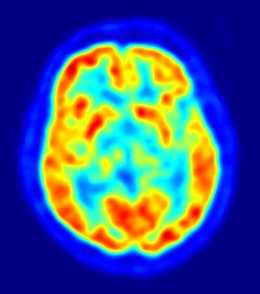

Los pacientes también se sometieron a imágenes por resonancia magnética funcional (fMRI) e imágenes de tensor de difusión (DTI, en sus siglas en inglés) antes, a mitad, al final y un mes después de la fase de rehabilitación. fMRI muestra que se activan áreas del cerebro mientras el paciente realiza una tarea y DTI revela la integridad de las fibras dentro de la materia blanca que conecta las zonas funcionales del cerebro.

Una comparación de los resultados pre y postrehabilitación reveló una reorganización en las regiones del cerebro responsables de la función motora y un fortalecimiento gradual de la integridad de los tractos fibrosos. "Nuestra esperanza es que este dispositivo no sólo reduzca el tiempo de rehabilitación de pacientes con accidente cerebrovascular sino también que resulte en un mayor nivel de recuperación que el logrado con la atención actual estándar", concluye Prabhakaran.